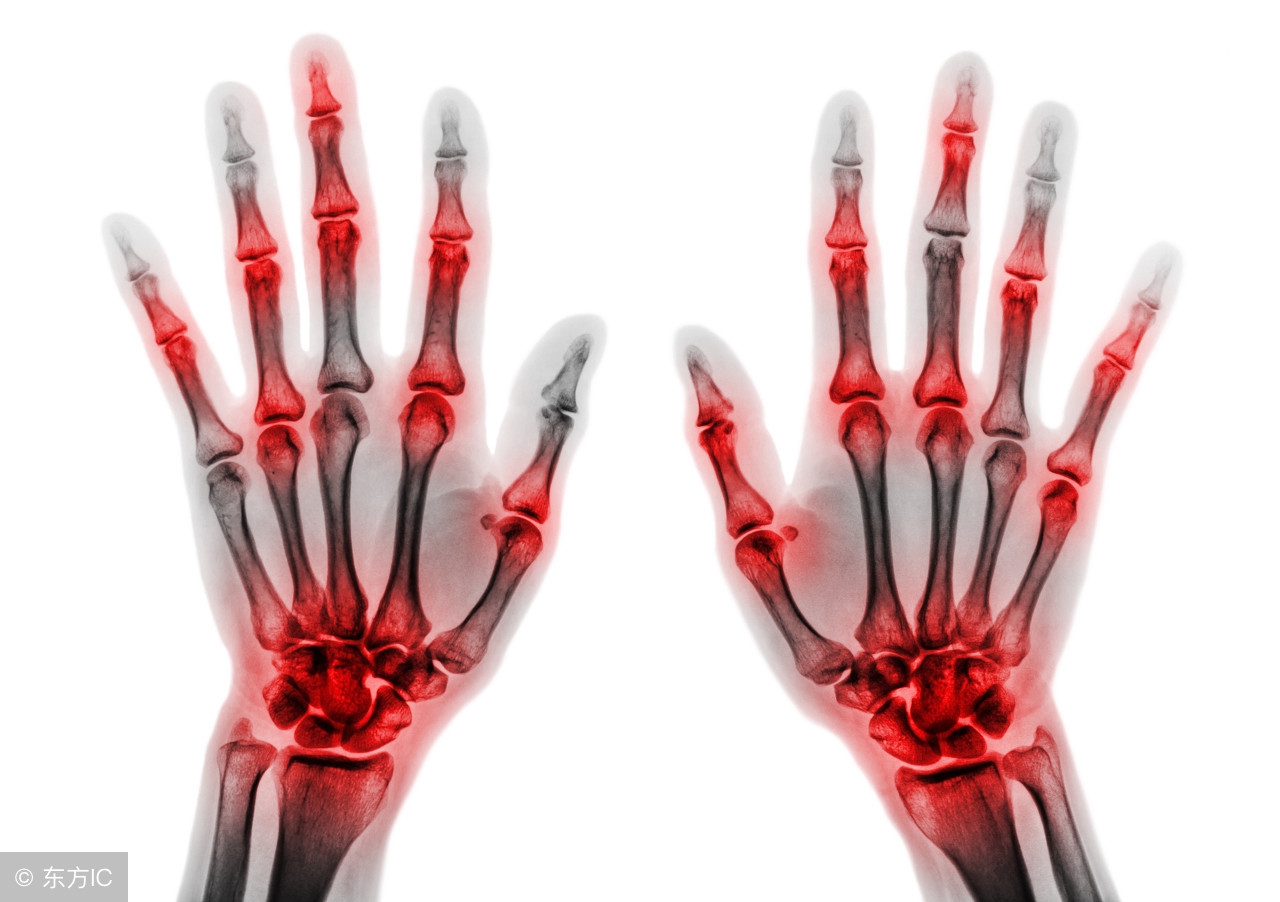

关节炎泛指发生在人体关节及其周围组织的炎性疾病,表现为关节的红、肿、热、痛、功能障碍及关节畸形,严重者导致关节残疾。

早期的类风湿性关节炎临床症状不典型,极容易被误诊或漏诊而耽误了最佳的治疗时期以致患者的关节功能异常。近年来,医学界越来越重视"治未病",对早期类风湿关节炎的筛查和防治被放到了非常突出的位置。若患者尚处于早期关节炎阶段时,就能被筛查和诊断为类风湿性关节炎,并抓住"窗口期"予以有效治疗,将对提高临床疗效和改善患者生活质量有着重大意义。

对于类风湿关节炎,目前尚无彻底根治方法,但通过早期筛查并给予规范化治疗能明显控制病情进展、改善临床症状、防止关节变形和残疾;早期筛查是实现类风湿关节炎早期治疗的前提和关键,现在早期类风湿关节炎的筛查是否引起了大家的注意呢。

类风湿关节炎是一种常见的慢性进行性致残性多关节炎(具有变化不定的系统改变),常带来沉重的经济负担。只有早期诊断、早期给予规范治疗才可能成功地减少关节破坏和功能丧失,就像我们老祖宗说的"上工治未病"!